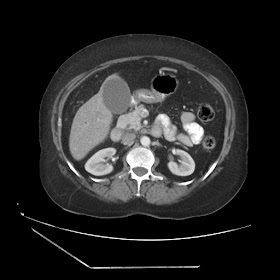

A 70 years old woman with Obstractive jaundice & palpable GB

Latest Radiological images: